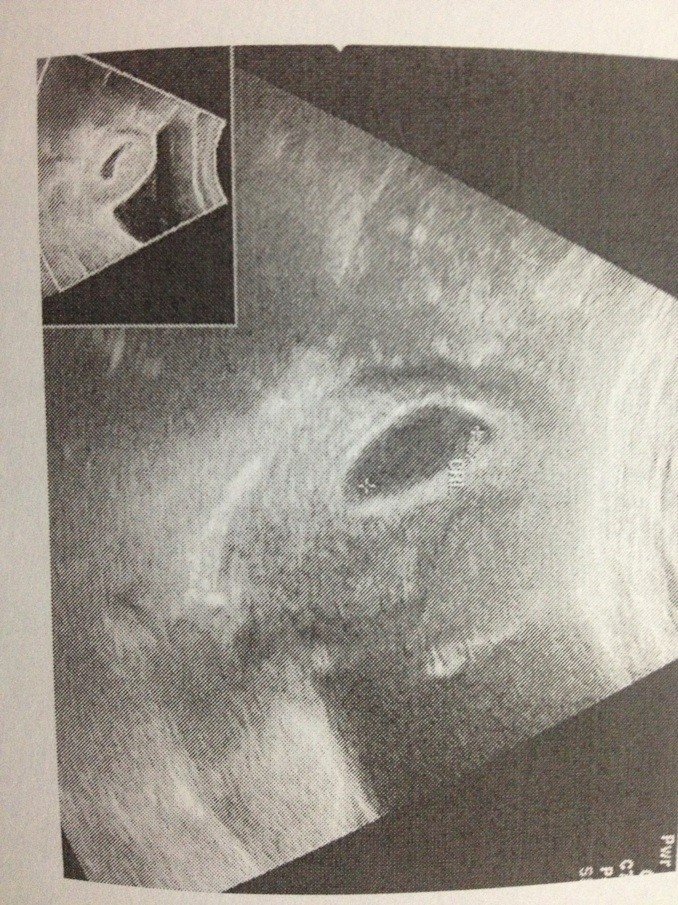

拜求我怀的是男生还是女生?孕囊大小3.9cmX3.5cmX1.3cm,孕芽0.49cm,早孕六周

您好,人们常说如果孕囊是长形的就是男孩子,如果孕囊是圆形的昌抹就是女儿。但是这个是不准的呢,也有的是长形的生了女儿,圆形的生了儿子的。所以只要宝逝串卜宝健康就舞府好,男女都一样。